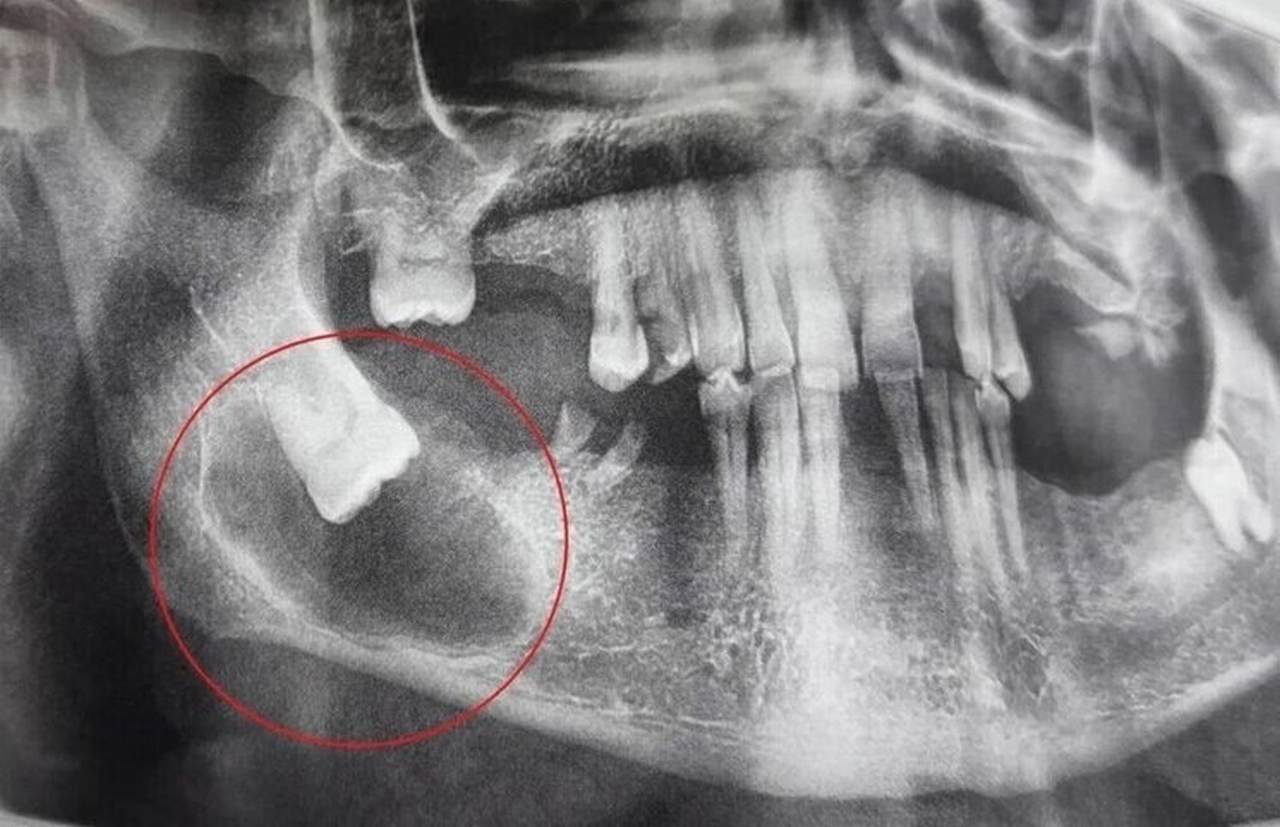

Детальная диагностика подтвердила, что зуб мудрости остался в кости, заняв горизонтальное положение. Вокруг его коронки и части корня сформировалась фолликулярная киста, которая постепенно разрушала костную ткань челюсти.